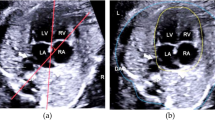

Detecting cardiac abnormalities between 14 and 28 weeks of gestation with an apical four-chamber view is a difficult undertaking. Several unfavorable factors can prevent such detection, such as the fetal heart’s relatively small size, unclear appearances in anatomical structures (e.g., shadows), and incomplete tissue boundaries. Cardiac defects without segmentation are not always straightforward to detect, so using only segmentation cannot produce defect interpretation. This paper proposes an improved semantic segmentation approach that uses a region proposal network for septal defect detection and combines two processes: contour segmentation with U-Net architecture and defect detection with Faster-RCNN architecture. The model is trained using 764 ultrasound images that include three abnormal conditions (i.e., atrial septal defect, ventricular septal defect, and atrioventricular septal defect) and normal conditions from an apical four-chamber view. The proposed model produces a satisfactory mean intersection over union, mean average precision, and dice similarity component metrics of about 75%, 87.80%, and 96.37%, respectively. Furthermore, the proposed model has also been validated on 71 unseen images in normal conditions and produces 100% sensitivity, which means that all normal conditions without septal defects can be detected effectively. The developed model has the potential to identify the fetal heart in normal and pathological settings accurately. The developed deep learning model's practical use in identifying congenital heart disorders has substantial future promise.